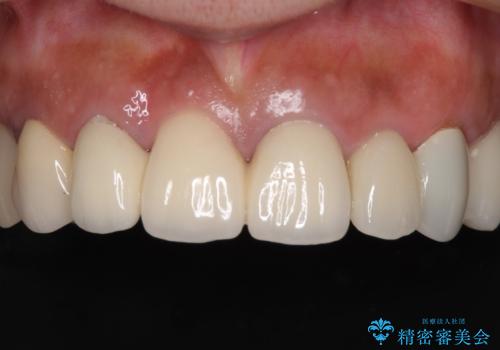

憧れの白い歯に 全顎セラミック治療

- 60歳を越え、黄ばんだ前歯をセラミッククラウンできれいな口元にしたいとのことで来院された患者様です。

診察したところ、前歯は反対咬合であり、その影響で抜歯が必要な奥歯があることが分かりました。

抜歯が必要な奥歯は、インプラント並びにブリッジにより補綴を行い、上下前歯は反対咬合を改善させるように補綴治療を行うこととしました。

健全な歯を削ってセラミッククラウンに置き換えることは、本来避けるべき治療と考えますが、今回は①患者様が60歳を越えていること、②要改善の咬合により抜歯が必要な奥歯があること、③反対咬合の前歯改善の手段としてセラミック治療が選択肢にあることなどから、全顎的なセラミック治療を行うこととしました。